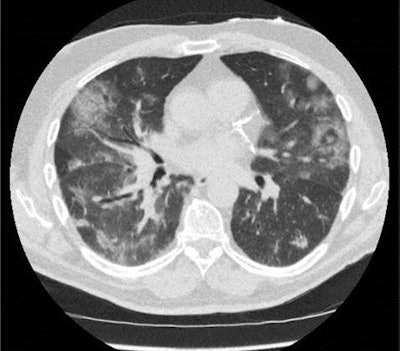

Because CT is superior to x-ray for detecting and assessing COVID-related lung involvement, Radboud radiologists have opted for low-dose CT as their primary imaging tool as an adjunct to reverse transcription PCR testing for diagnosing the disease in patients with moderate to severe symptoms presenting at the emergency room.

Moreover, CO-RADS is now a standardized tool to assess the suspicion of pulmonary involvement of COVID-19 on chest CT. The system was developed in mid-March by the COVID-19 reporting group of the Dutch Society of Radiology, inspired by similar systems such as BI-RADS, Lung-RADS, or CAD-RADS, and in response to increasing reports that PCR tests may be initially negative in COVID-19 patients.

CO-RADS encodes the suspicion of lung involvement of COVID-19 on a scale from 1 (very unlikely) to 5 (very likely) and is meant to be combined with a CT severity score that assesses the extent of pulmonary involvement. It is aimed at high-prevalence settings such as when hospital admission is considered and COVID-19 is part of the differential diagnosis.

Prokop pointed to a validation study of CO-RADS on more than 100 randomly selected cases with moderate to severe symptoms who were scanned using low-dose chest CT at the medical center. Using a positive PCR test result as the gold standard, receiver operating characteristic analysis of CO-RADS yielded an average area under the curve of more than 0.90.

"In patients presenting with moderate to severe symptoms, 20% to 50% of whom have the disease, the CO-RADS score works well," he noted. "The CT protocol requires a dose-length product of some 40 mGy-cm, which translates into an effective radiation dose of well below 1 mSv. COVID-19 can kill, so we are happy with this optimized dose."